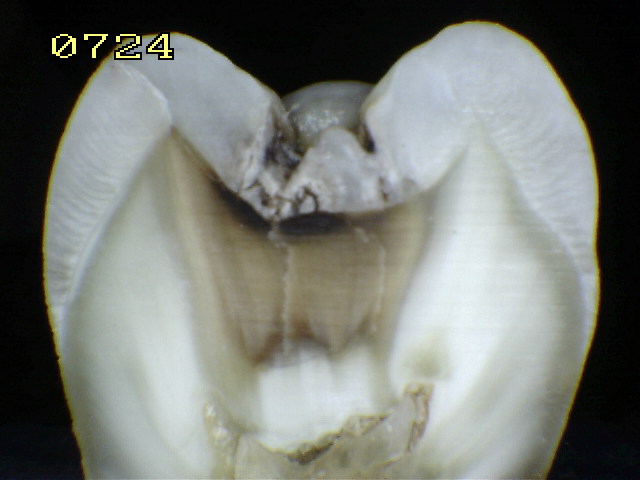

Espécimen Nº 25 |

|

Corte sagital en A fosa mesial y en B

fosa distal |

Corte A

fosa mesial es un código 2 histológico. |

Corte B

en fosa distal es un código 1 histológico |